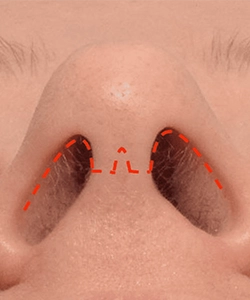

اصلاح افتادگی یا پهنی نوک بینی، باریکسازی متعادل

تقارن پرههای بینی و بهبود زاویه بینی و لب بالا

ترمیم دریچههای داخلی/خارجی بینی برای جلوگیری از کلاپس هنگام دم

برشها داخل بینی انجام میشود؛ هیچ برش خارجی روی کلوملا دیده نمیشود.

انتخاب روش باز یا بسته پس از معاینه و بر اساس آناتومی و هدف بیمار تعیین میشود.